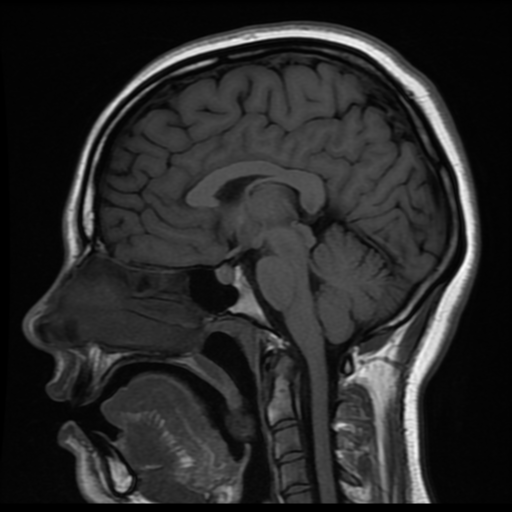

This project bridges neuroimaging and physical fabrication to create an interactive, haptic learning tool for neuroanatomy. By converting a T1-weighted MRI slice into a 3D-embossed tactile map with conductive landmarks, the system enables game-based learning inspired by Operation, promoting spatial understanding through touch and immediate feedback.

Source data: T1-weighted sagittal MRI from a healthy 20-year-old female (case 37605)